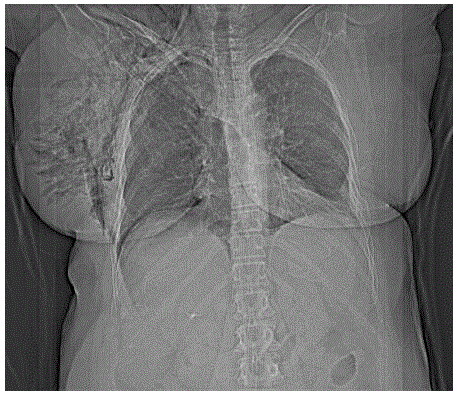

Mulher de 64 anos, vítima de atropelamento, dá entrada no serviço de emergência transportada pela equipe de resgate. Refere dor torácica do lado direito. Apresenta frequência respiratória: 25 ipm, Sat. O2: 90%; frequência cardíaca: 120 bpm; pressão arterial: 140x90 mmHg; Glasgow coma escore: 15. Ao exame clínico murmúrio vesicular diminuído do lado direito, mama direita 3x o tamanho da mama esquerda, enfisema de subcutâneo no hemitórax direito. O raio-X de tórax mostra:

O tratamento mais adequado neste momento é: